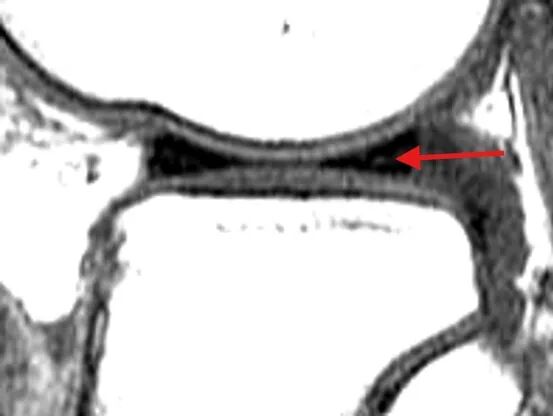

对于怀疑半月板损伤患者,应进行膝关节核磁共振(MRI)检查,该检查无创、分辨率高,对半月板损伤有很高的敏感性和特异性。根据半月板损伤的MRI表现,可以分成3级:

0 级

为正常的半月板,呈均匀的低信号,半月板形态规则。

I 级

表现为不与关节面相接触的灶性椭圆形或球形高信号。

II 级

表现为水平、线性半月板内高信号,可延伸至半月板的关节囊缘,但未达到半月板的关节面。

III 级

半月板内高信号达到上或下关节面。

I级、II级损伤通常为退变信号,不需要医学干预。III级损伤显示高信号贯通到半月板表面了,等同撕裂,一般伴随症状,需要医学干预。